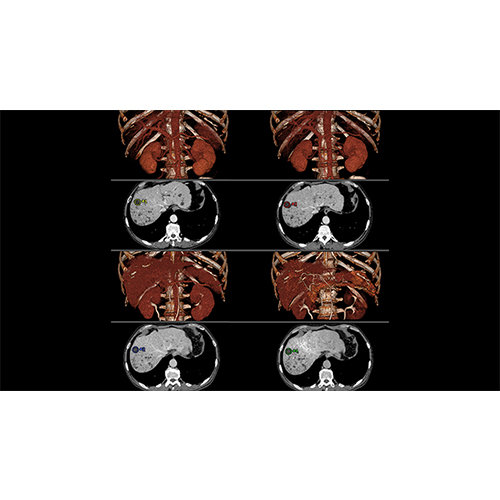

Multi-planar slicing.

Side-by-side comparative assessment for pre- and post-operative scans.